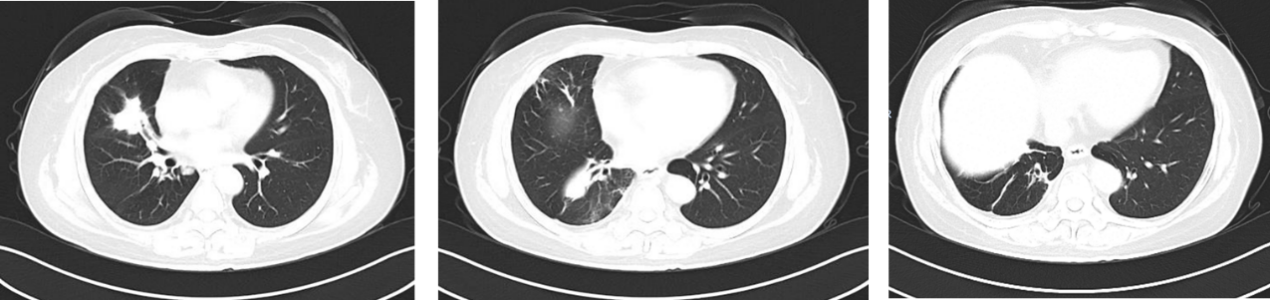

2024年5月-2024年6月,行2周期白蛋白紫杉醇治疗。

疗效评估:PD。

三线治疗:

2024年7月至2025年4月,行长春瑞滨软胶囊(40mg,每周一、三、五)口服治疗。

疗效评估:PR。